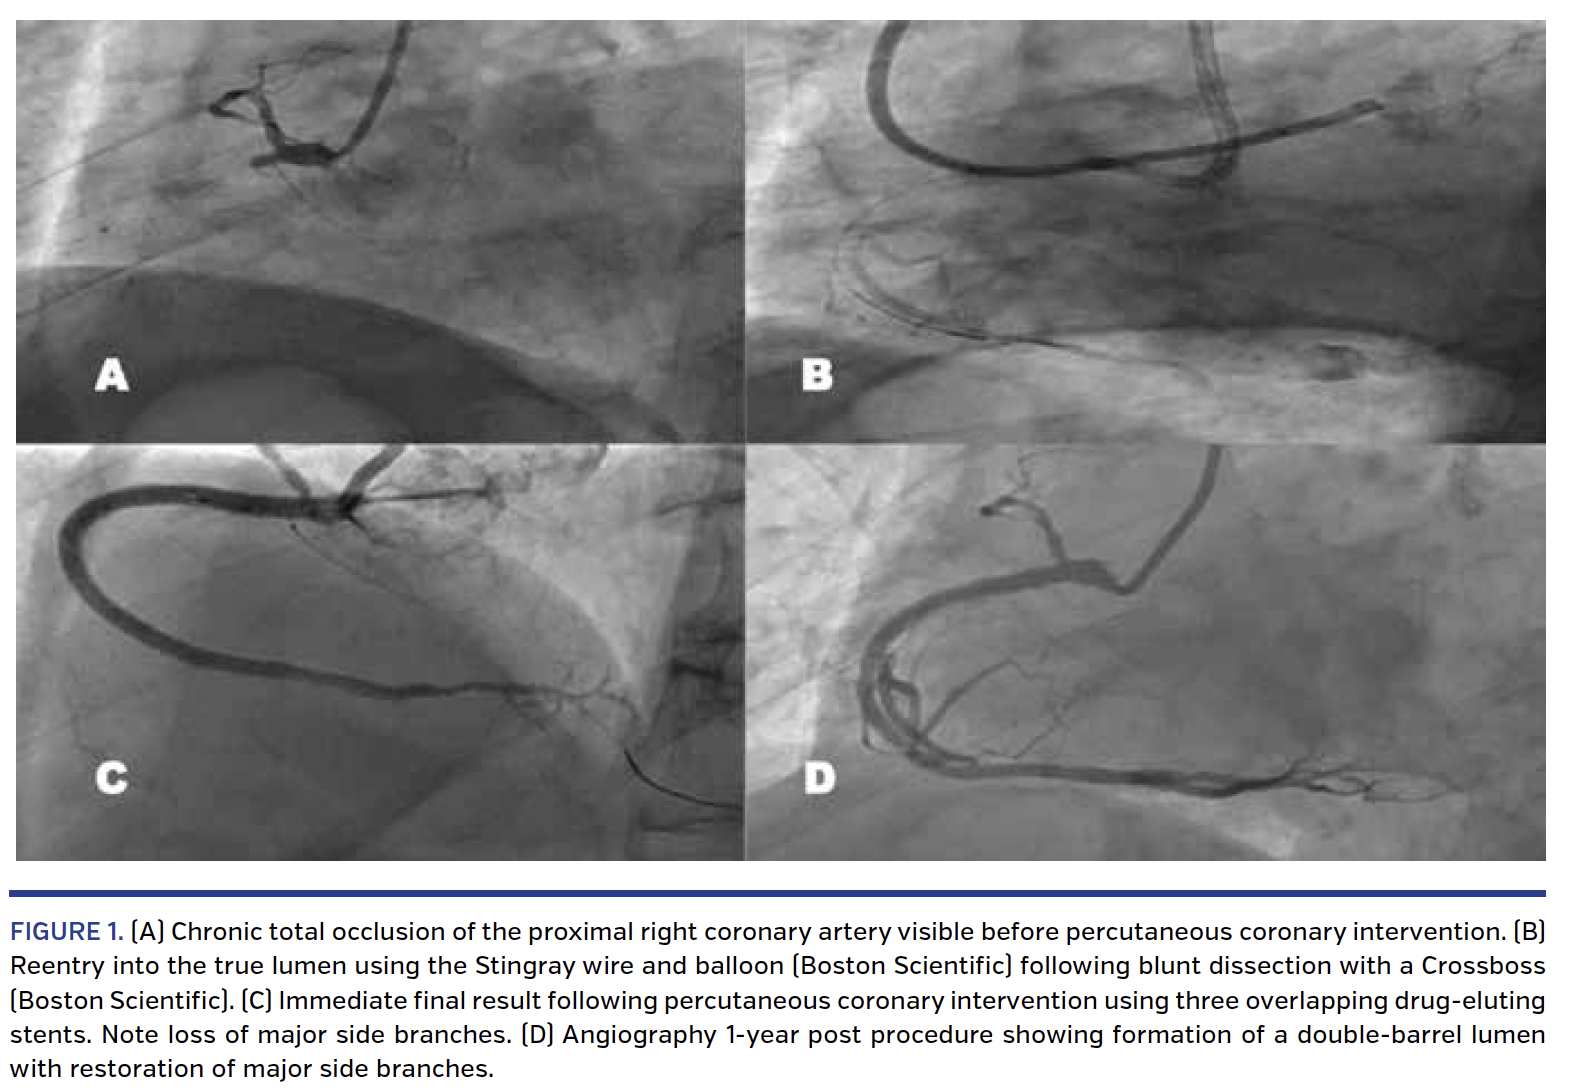

An 80-year-old man presented with Canadian Cardiovascular Society class 2 angina despite maximal tolerated medical therapy. His background included hypertension and a previous inferior myocardial infarction in 1991, which had been treated medically. He had a documented CTO of the right coronary artery on angiography in 2005. A myocardial sestamibi perfusion scan showed moderate inferior peri-infarctional ischemia. His echocardiogram confirmed an ejection fraction of 50% with inferior hypokinesis. Right ventricular function was normal. Work-up angiography confirmed a CTO commencing at the proximal right coronary artery (Figure 1A) with a long (>20 mm) segment of occlusion with the distal vessel being collateralized from the left coronary system. There was only moderate disease of the left coronary system involving the left anterior descending coronary artery.

Percutaneous coronary intervention was performed with dual femoral arterial access. The initial approach was to attempt antegrade dissection/reentry with a bailout retrograde approach using the reverse controlled antegrade and retrograde tracking (CART) strategy if required. Successful antegrade subintimal blunt dissection with the Crossboss system (Boston Scientific) was performed followed by reentry into the true lumen with the Stingray catheter (Boston Scientific) (Figure 1B). Two overlapping drug-eluting stents were placed from the proximal to the mid-vessel with a pleasing angiographic result (Figure 1C).

Post procedure, the patient’s angina resolved and he exercised regularly. He returned for repeat coronary angiography 1 year after CTO-PCI for investigation of an episode of atypical chest pain. Coronary angiography showed no change in appearance in his left coronary system. The two stents in his right coronary artery were widely patent, but there was evidence of formation of a double-barrel lumen. Of note, this had led to return of function and preservation of major side branches, in particular a large right ventricular branch (Figure 1D). Right ventricular function was normal on echocardiogram.